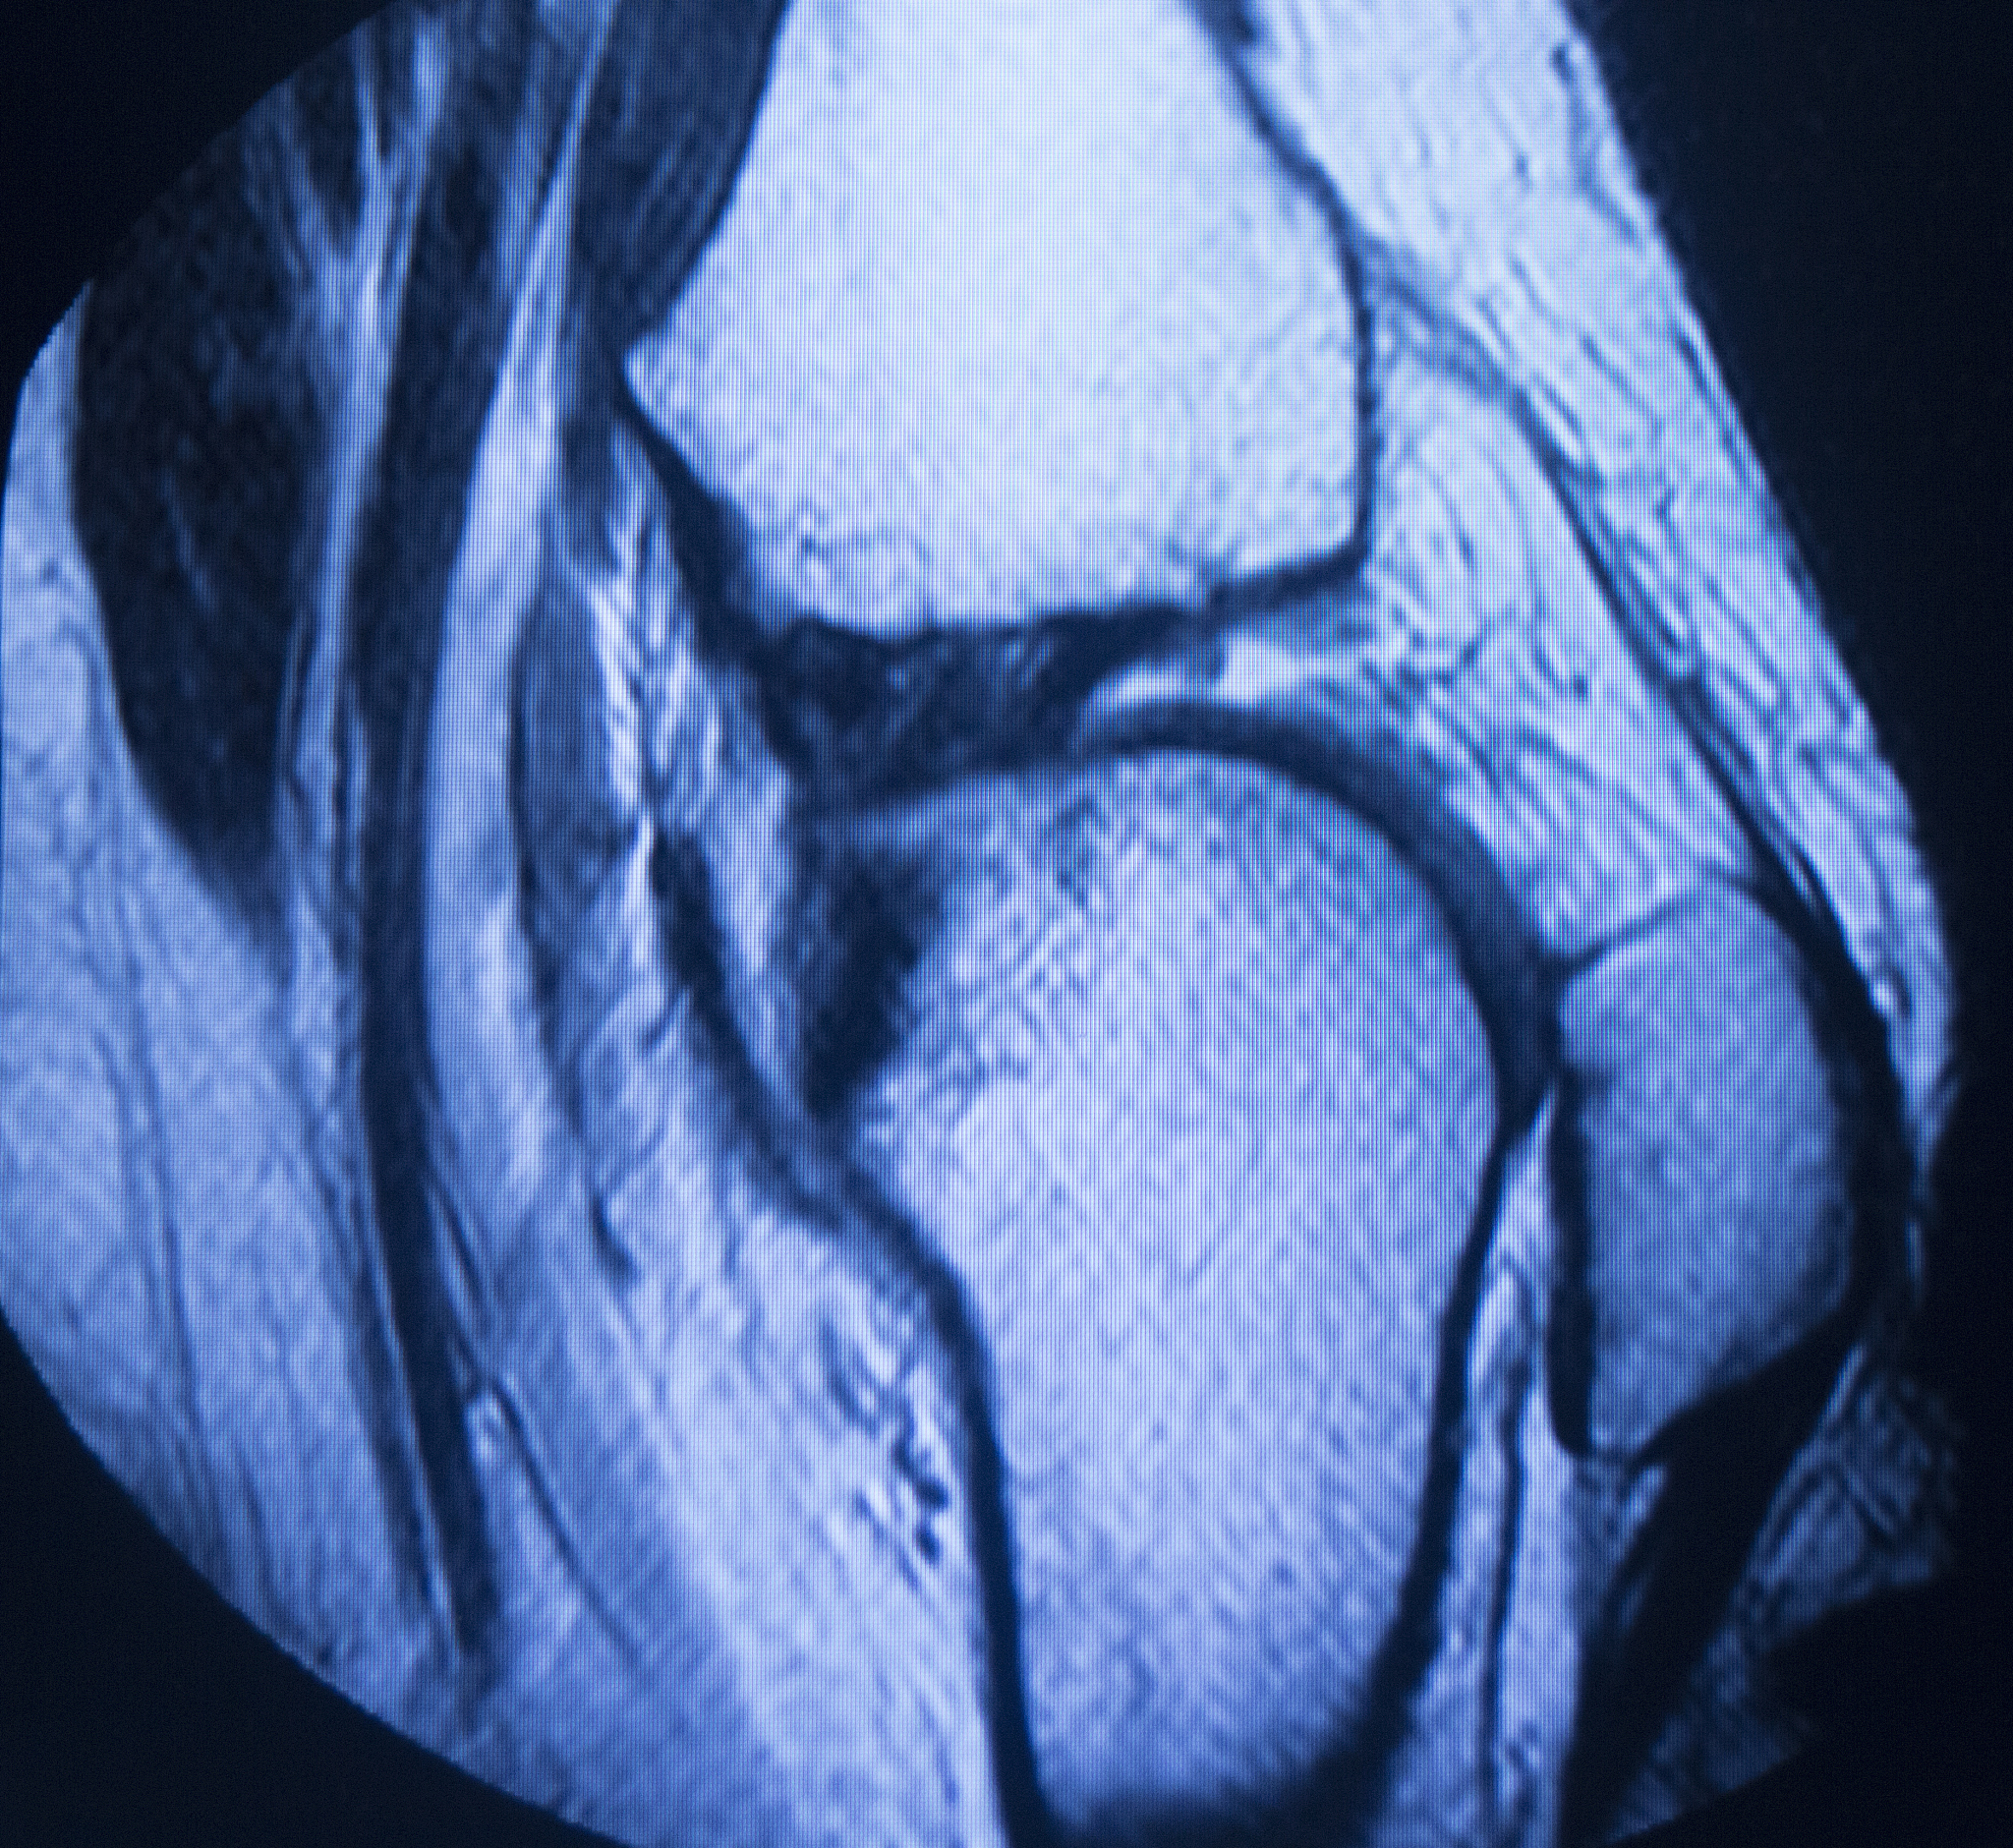

韧带损伤MRI分级:Ⅰ级、Ⅱ级、Ⅲ级分别代表什么?

韧带损伤是运动中常见的损伤之一,核磁共振(MRI)是评估韧带损伤的重要影像学检查方法。根据MRI表现,韧带损伤通常分为Ⅰ级、Ⅱ级和Ⅲ级。

• Ⅰ级韧带损伤表示韧带部分撕裂,但仍保持连续性;* Ⅱ级韧带损伤表示韧带纤维有损伤,但未完全断裂;* Ⅲ级韧带损伤表示韧带基本正常,可能存在轻微的拉伤。

需要强调的是,MRI分级只是评估韧带损伤严重程度的指标之一,还需要结合临床症状、体征以及其他检查结果进行综合判断。建议患者及时就医,在专业医生指导下进行治疗和康复。